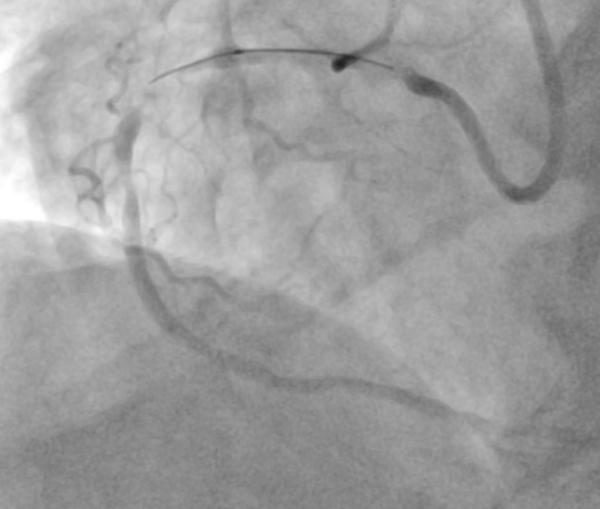

76 岁男性患者因急性 ST 段抬高型心肌梗死合并心源性休克紧急入院,既往有冠脉介入史,此次造影显示:左主干 90% 慢性狭窄,左前降支支架近端和远端新的原发性次全狭窄,优势血管右冠脉远段血栓合并重度钙化,左心室射血分数仅 25%,血流动力学极不稳定,需机械循环支持辅助手术。

手术选用Medoo MeCross CTO半顺应性PTCA球囊扩张导管 2.0×15mm进行靶病变预扩张,球囊顺利通过指引导管直达病变部位,推送性、跟踪性优异,通过重度钙化血栓病变无明显阻力,与国际一线品牌性能相当。充胀至 14 个大气压时,球囊完全均匀扩张,无狗骨效应;放气迅速有效,撤出过程无阻力,全程无手术并发症。且球囊包装精简,急诊场景下可快速拆封准备,大幅节省术前时间,适配急诊救治的高效需求。后续联合其他器械完成支架植入后,患者血流动力学恢复稳定,顺利转至 ICU 监护。